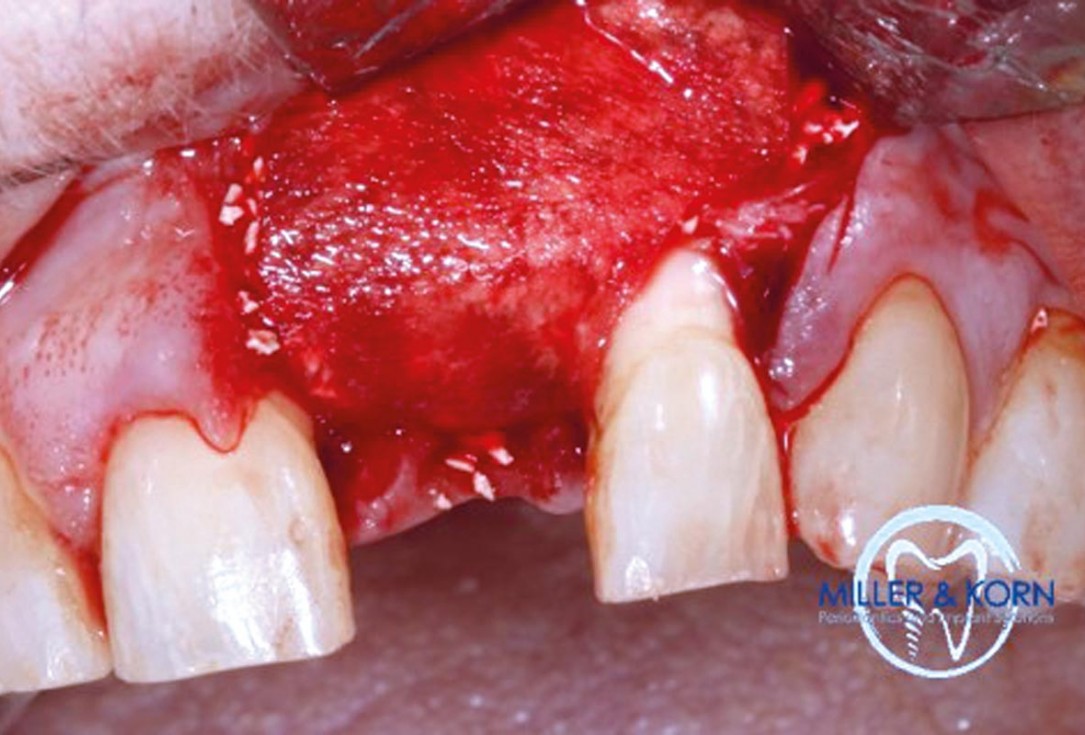

26/39 - Covering of the augmented area with a Jason® membrane sutured to the palatal flapImmediate implant placement and correction of horizontal and vertical bone loss using an allograft bone ring, cerabone® and Jason® membrane - Drs. Miller and Korn

-